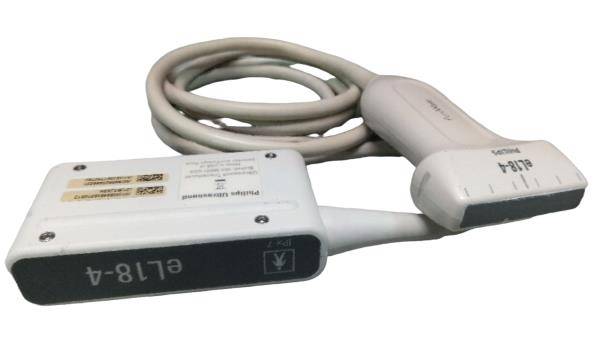

SONOSITE L25X LINEAR FOR M-TURBO EDGE S - Top-Notch Ultrasound Probe

SONOSITE L25X LINEAR FOR M-TURBO EDGE S-NERVE TRANSDUCER - Ultrasound Probe

The SONOSITE L25X LINEAR FOR M-TURBO EDGE S is a premier ultrasound transducer designed to provide high-quality imaging for a variety of clinical applications. This specialized probe is compatible with the SONOSITE M-TURBO EDGE system, a leading point-of-care ultrasound device that delivers exceptional image clarity and reliability. Whether you are in emergency medicine, regional anesthesia, or vascular procedures, the SONOSITE L25X LINEAR provides precise and reliable results every time.

Designed with advanced technology, the SONOSITE L25X LINEAR FOR M-TURBO EDGE S offers a frequency range that is optimal for superficial imaging, aiding healthcare professionals in obtaining detailed and accurate images. The probe's ergonomic design ensures ease of use during extended scanning sessions, reducing operator fatigue. SONOSITE, a brand known for its innovation and quality, ensures that every detail of the L25X LINEAR is tailored to meet the high demands of modern medical environments.

In addition to its superior imaging capabilities, the SONOSITE L25X LINEAR FOR M-TURBO EDGE S is built to withstand the rigors of everyday clinical use. Its durable construction means it can handle frequent cleaning and disinfection processes essential in maintaining hygiene standards in medical settings. Investing in this ultrasound probe not only enhances diagnostic accuracy but also ensures a reliable performance that stands the test of time.

The SONOSITE L25X LINEAR FOR M-TURBO EDGE S is also known for its quick-and-easy setup, which saves valuable time in fast-paced clinical settings. Furthermore, it offers seamless integration with the SONOSITE M-TURBO EDGE system, providing a user-friendly experience that complements the workflow of healthcare professionals. This leads to improved patient care and optimized clinical operations.

For any healthcare facility looking to enhance its ultrasound imaging capabilities, the SONOSITE L25X LINEAR FOR M-TURBO EDGE S is a worthy investment. Its high-resolution imaging, durability, and user-oriented design make it a standout choice in the market. With the SONOSITE L25X LINEAR, clinicians can perform accurate diagnoses, carry out intricate procedures with confidence, and ultimately, improve patient outcomes. Don't miss out on the opportunity to advance your practice with this exceptional ultrasound probe.